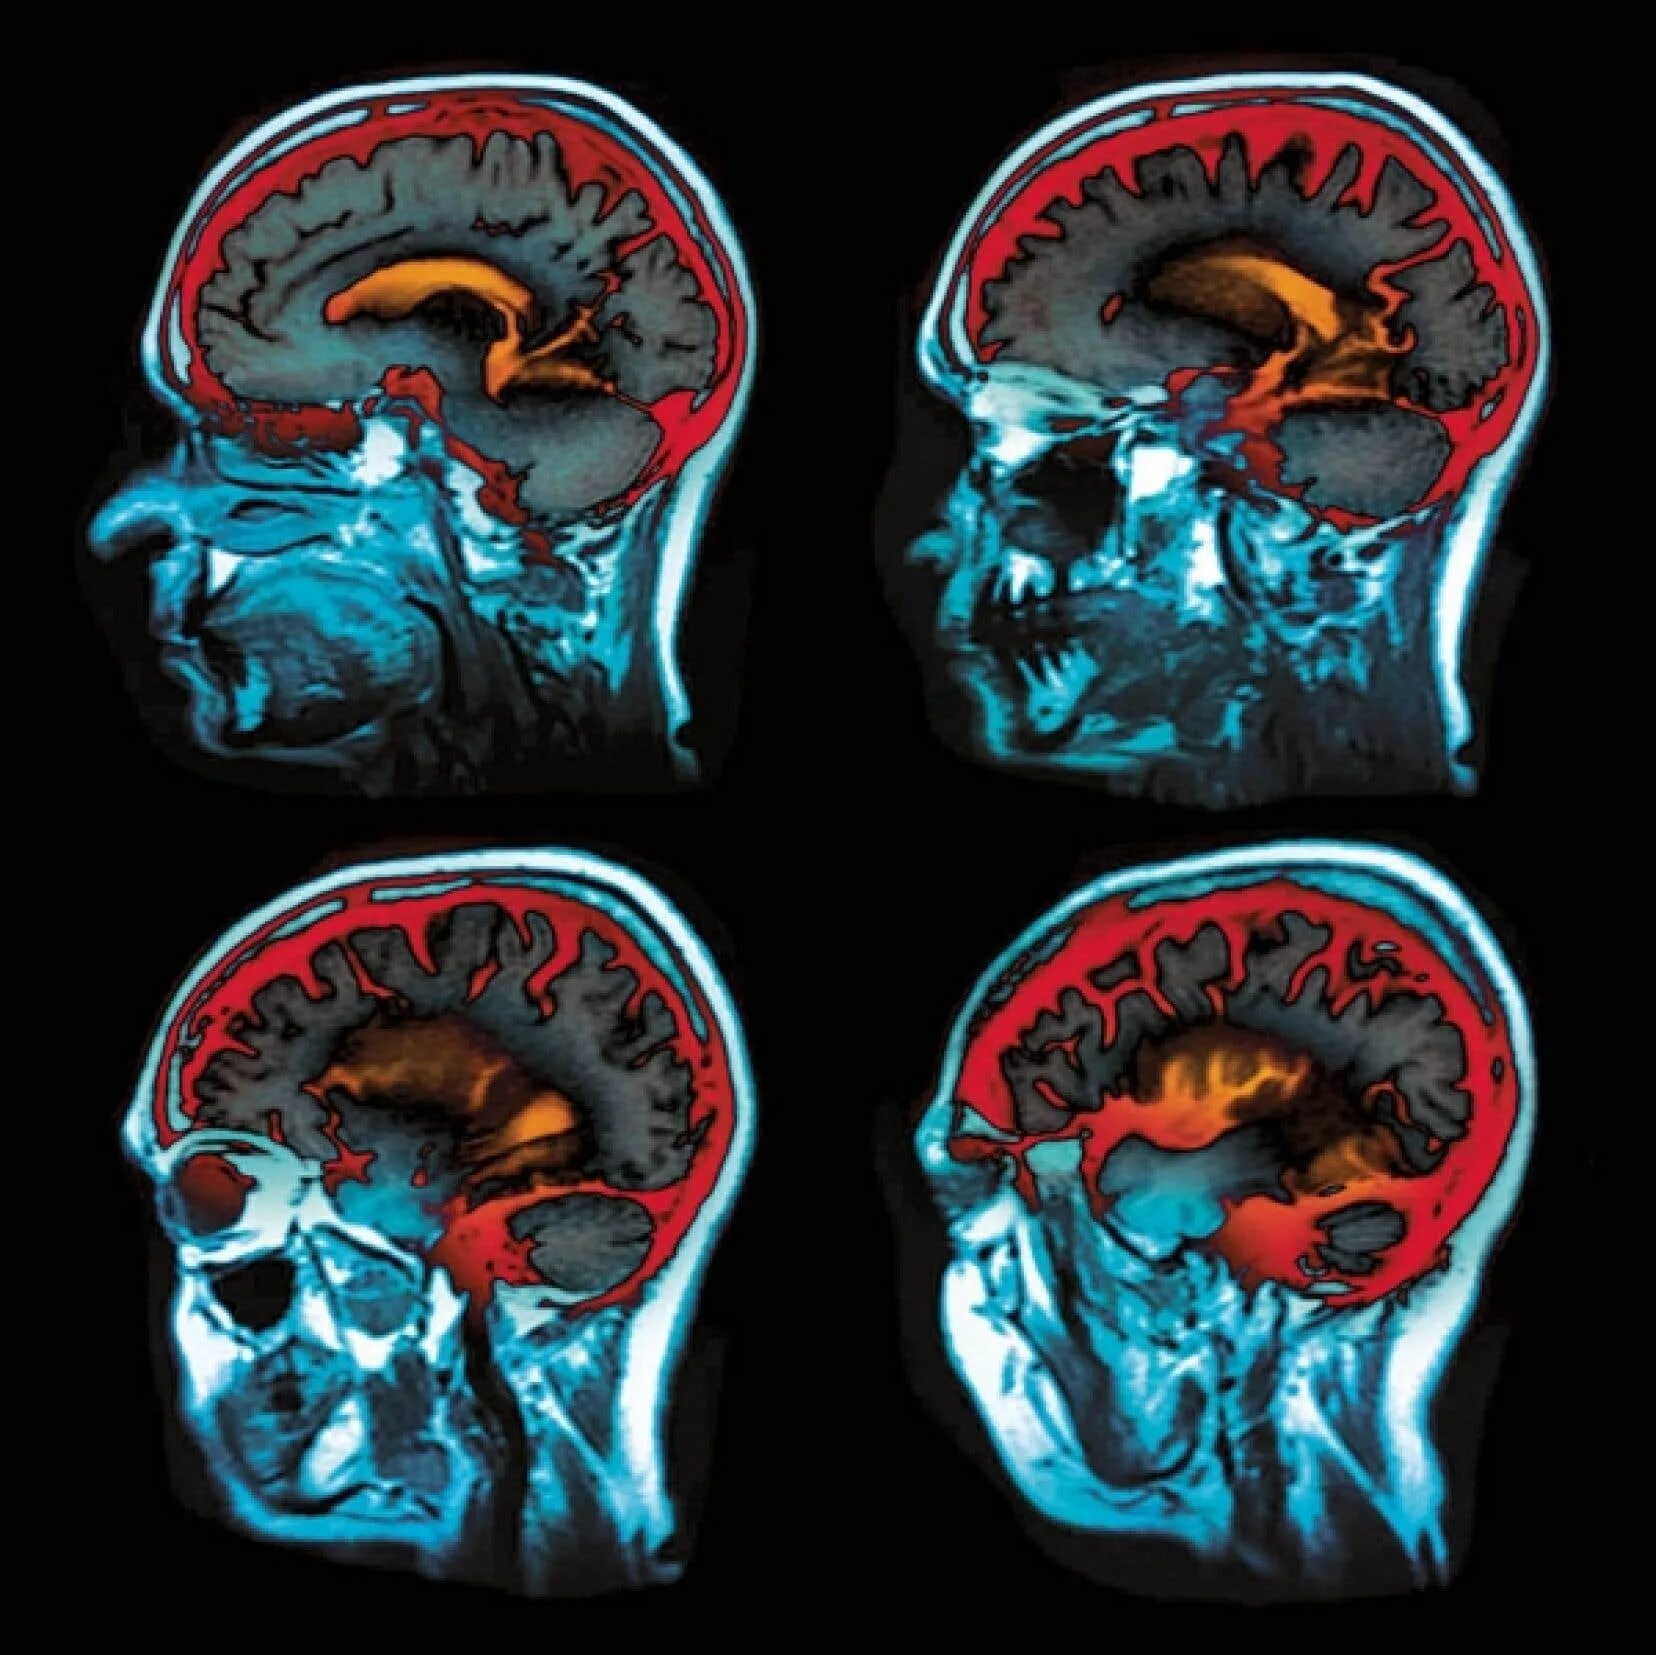

Мрт с контрастированием головного